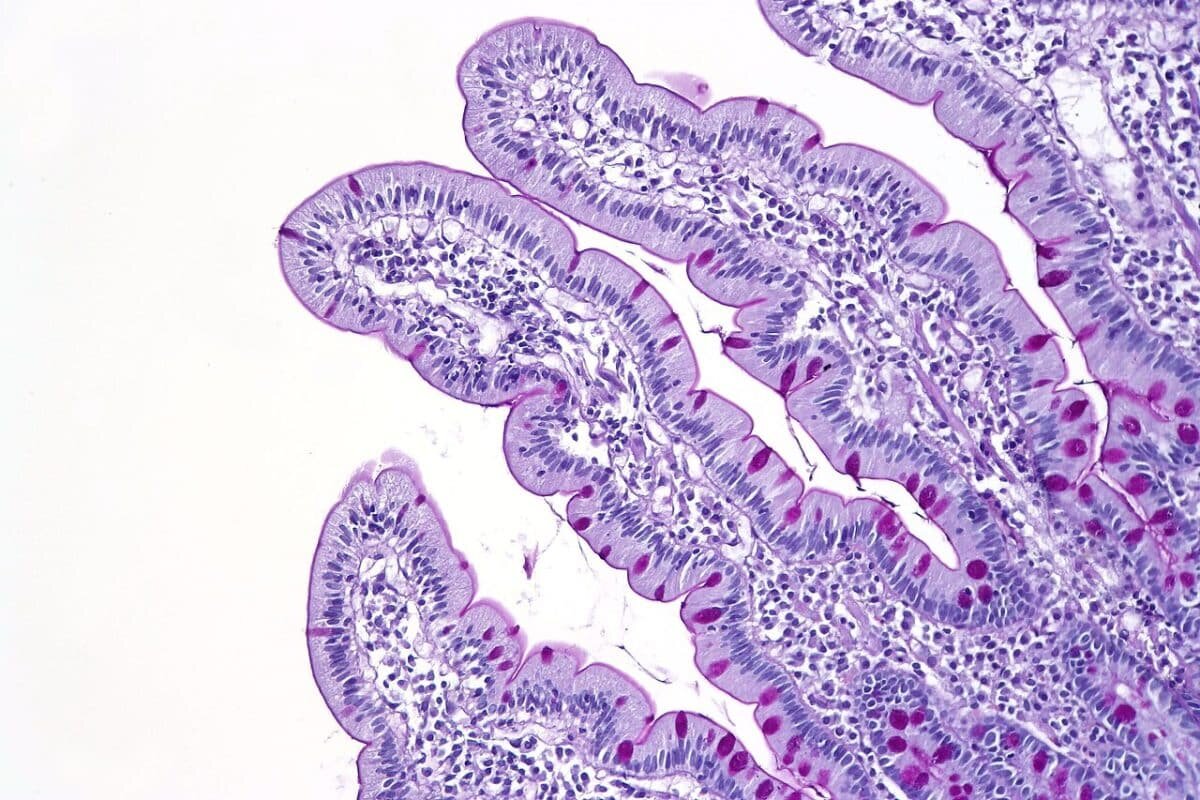

Ворсинки в двенадцатиперстной кишке / © CoRus13